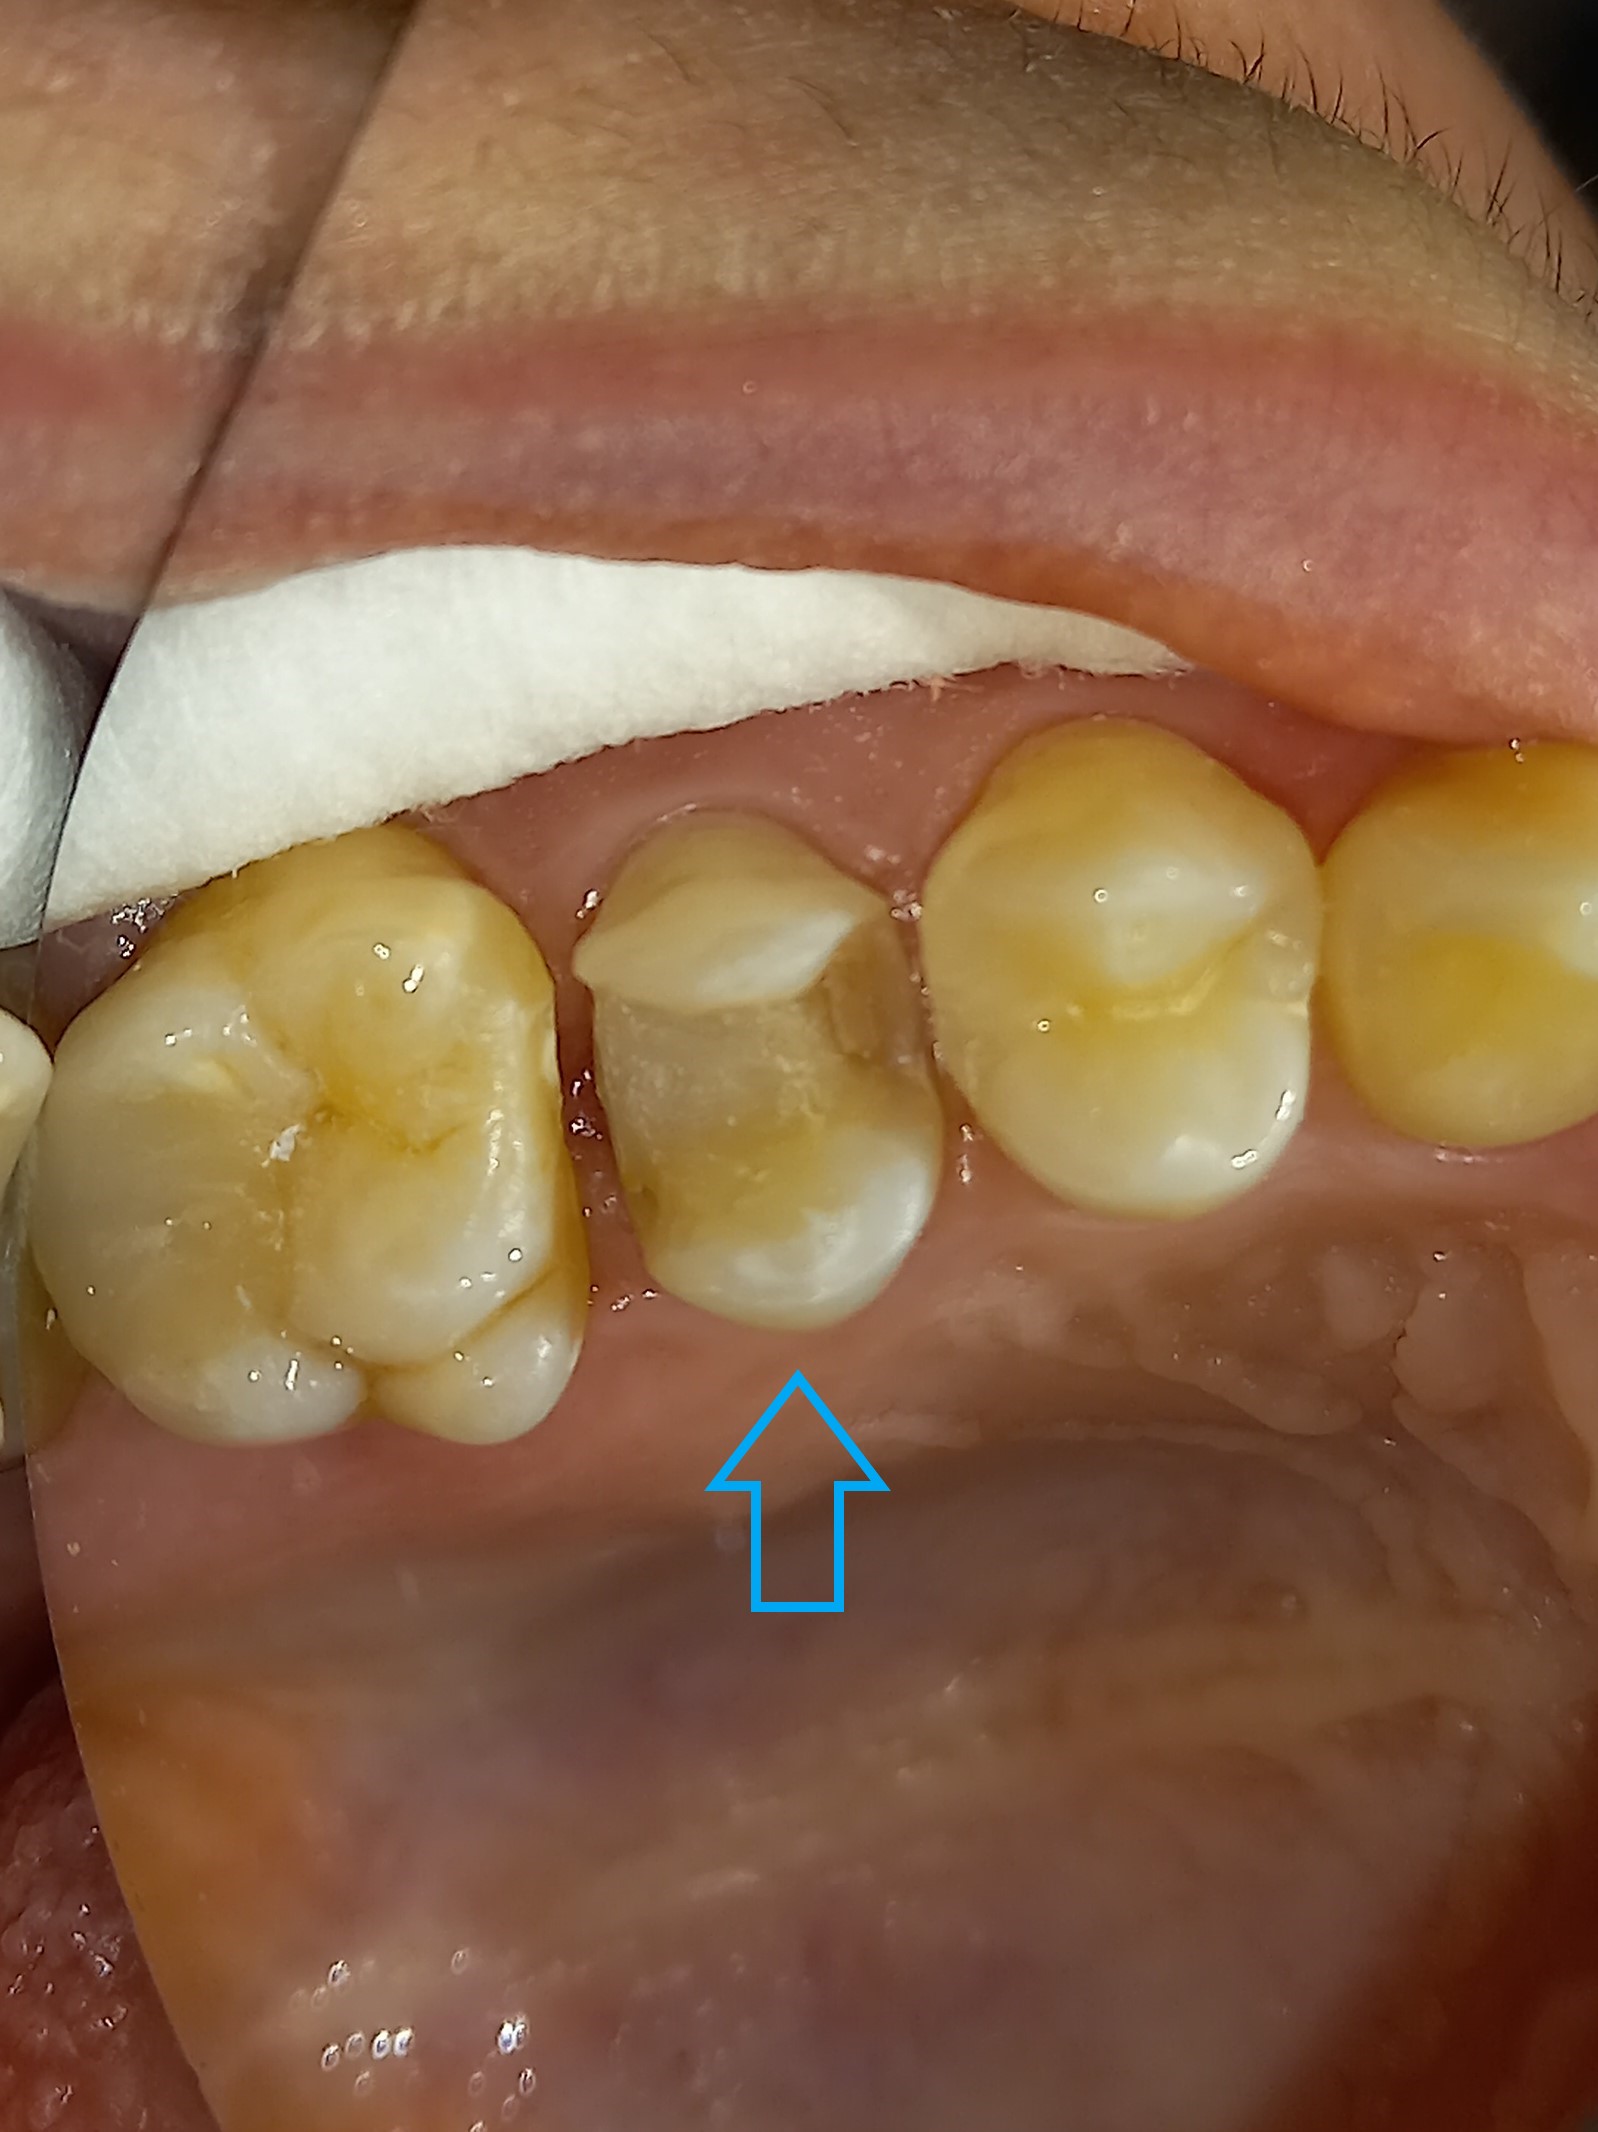

Αρχική εικόνα του παλιού μεγάλου σφραγίσματος

Κλινική εικόνα του μεγάλου οδοντικού ελλείμματος μετά την αφαίρεση του παλιού σφραγίσματος

Το ολοκεραμικό ένθετου στο εκμαγείο από τον οδοντοτεχνίτη

Τελική κλινική εικόνα του ολοκεραμικού επένθετου στο γομφίο